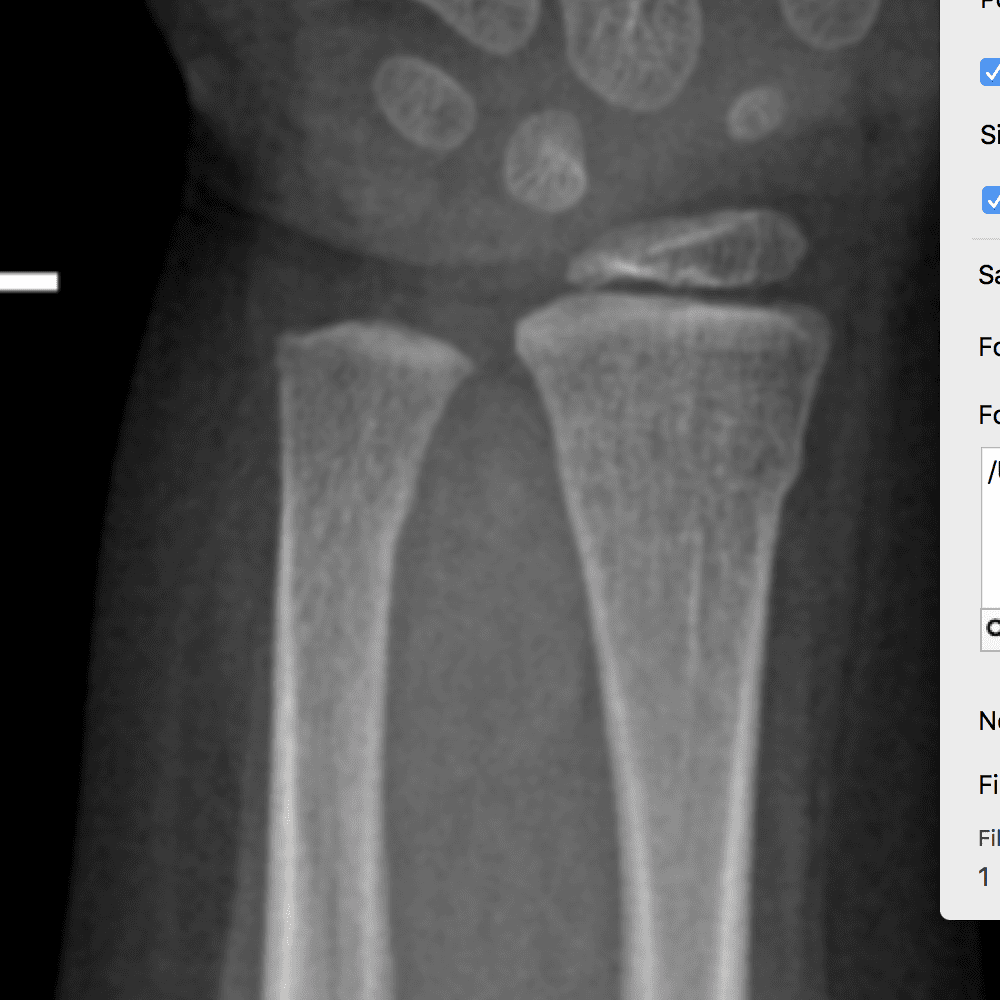

Simulates call by including subtle or difficult cases and some normals.

30 cases